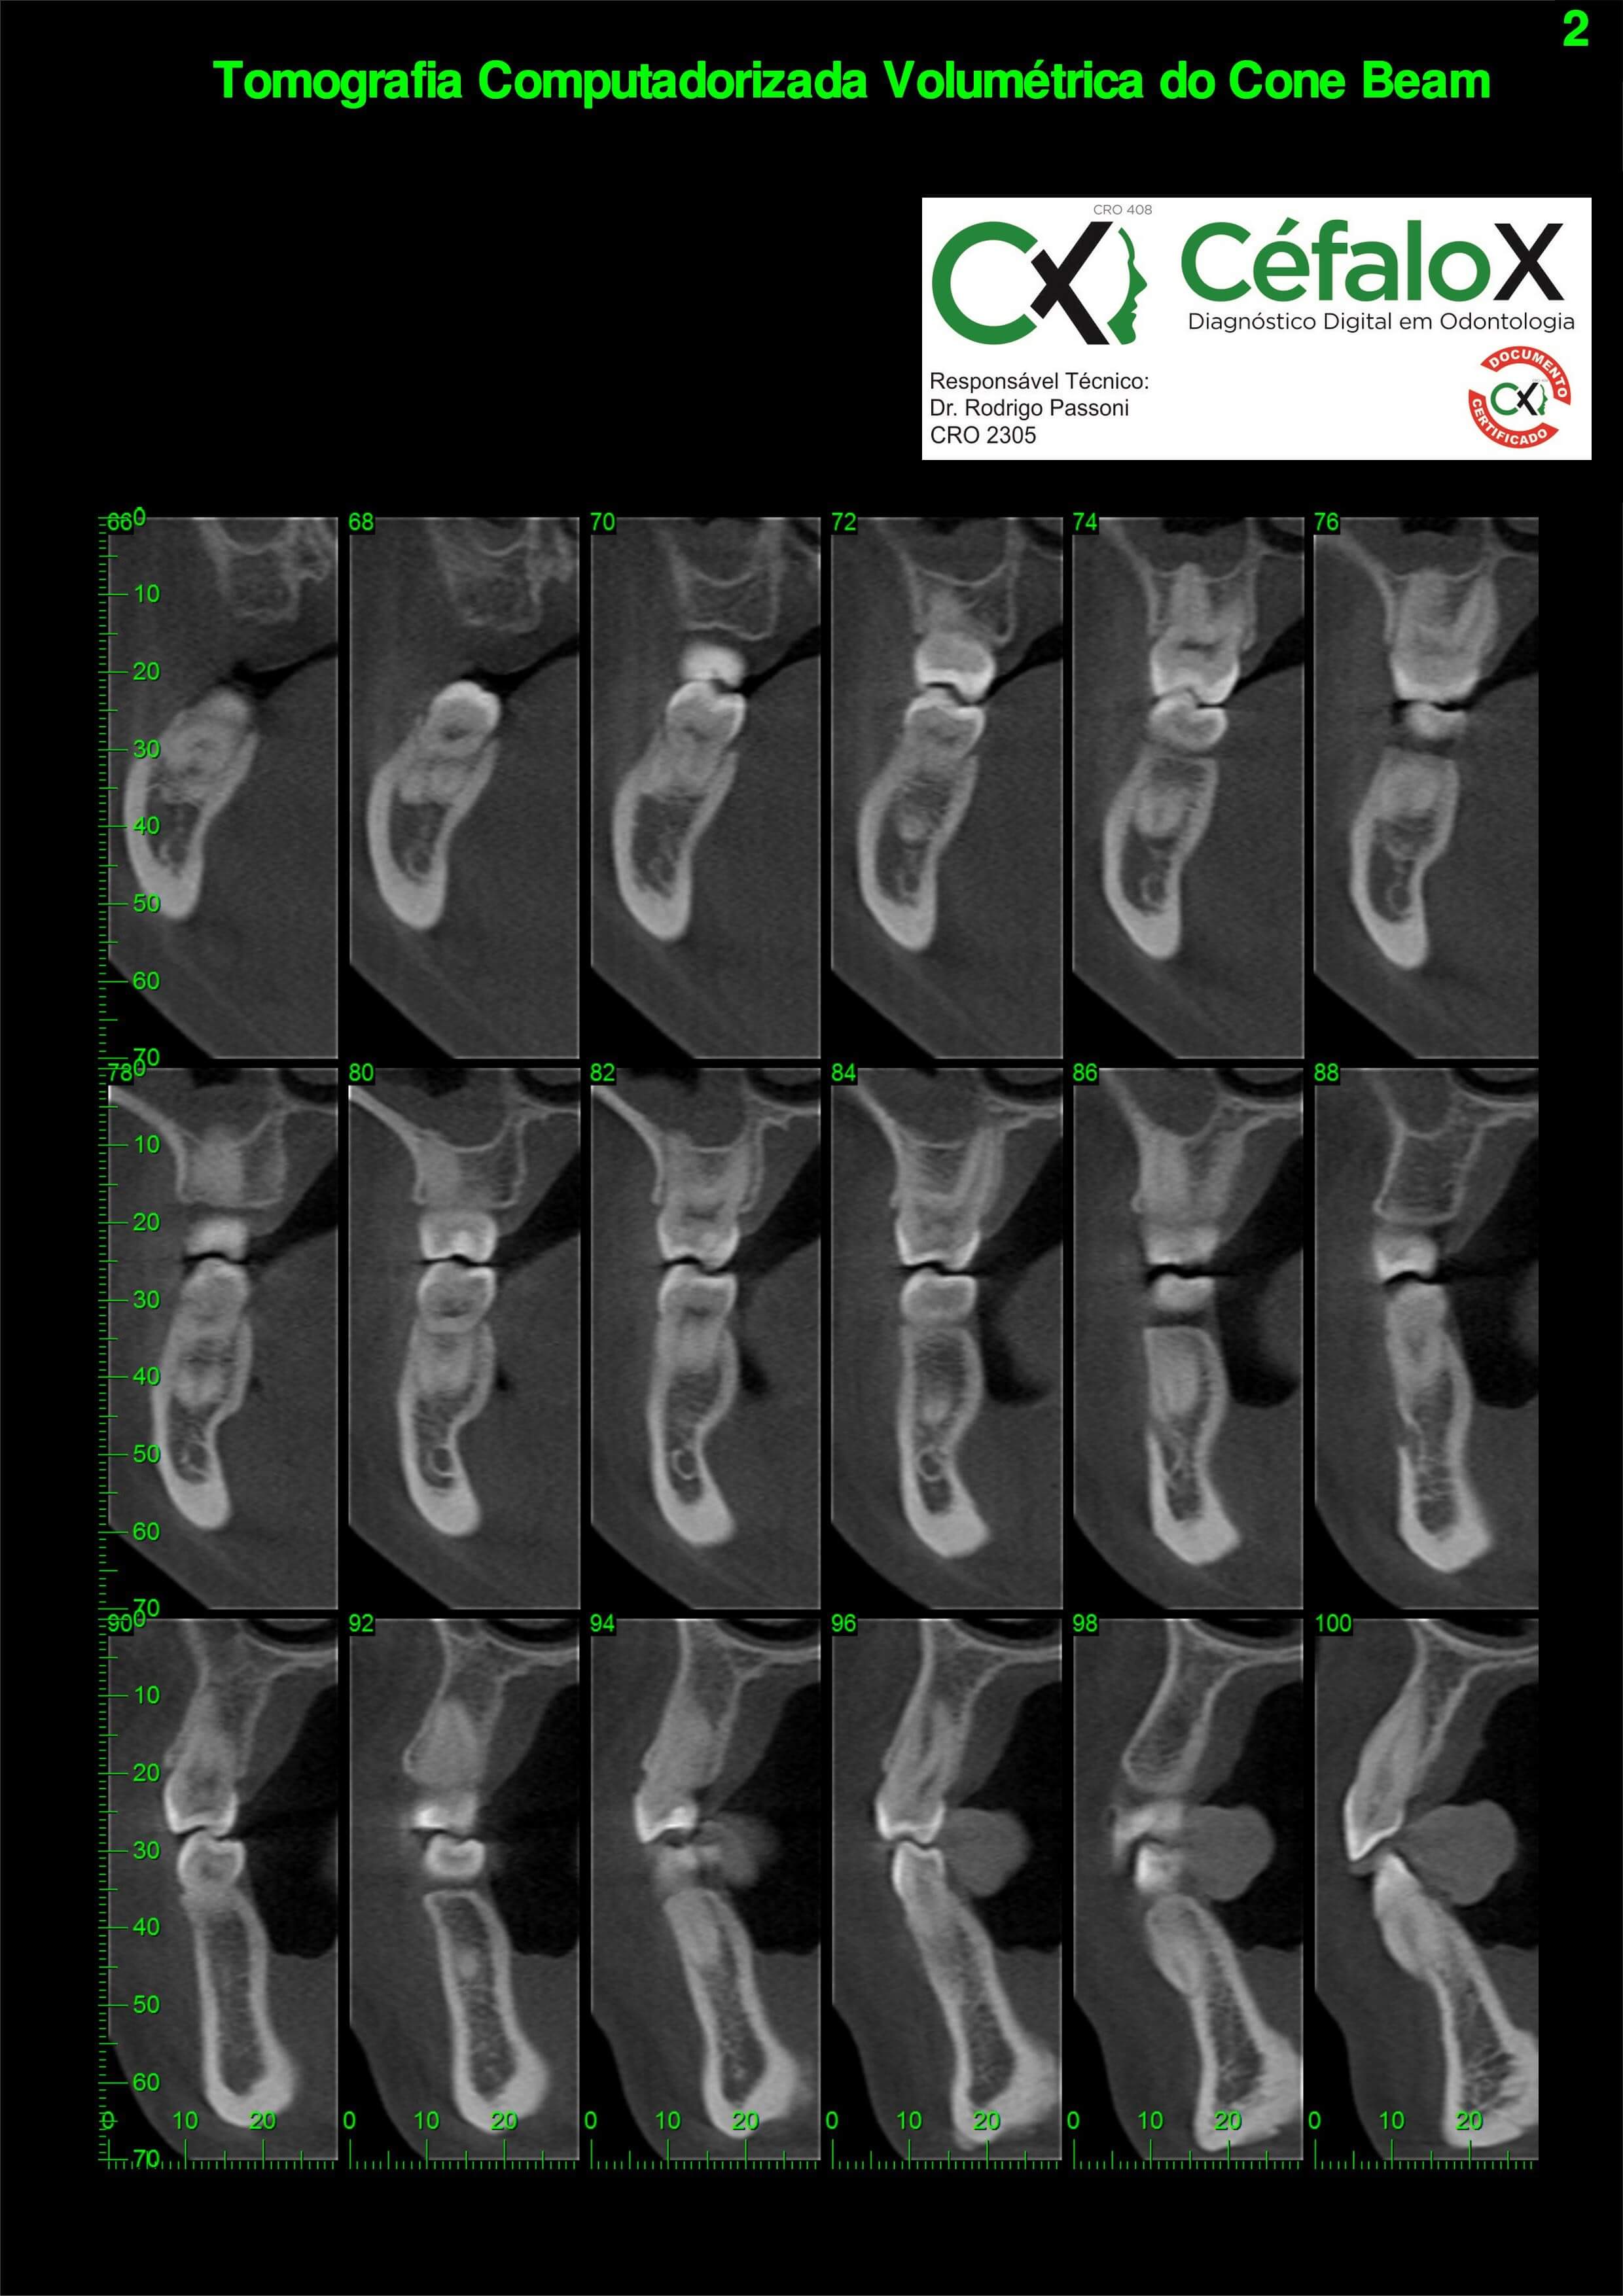

TC de face (do Hióide à Glabela), reconstrução 3D do tecido ósseo, radiografia panorâmica, telerradiografia lateral com traçado, cortes transversais e axial de maxila e mandíbula e arquivo DICOM- entregue em pasta de Pvc.

TC de face (do Hióide à Glabela), reconstrução 3D do tecido ósseo, radiografia panorâmica, telerradiografia lateral e frontal com traçado, cortes transversais e axial de maxila/mandíbula e arquivo DICOM – entregue em pasta de Pvc.

TC de face (do Hióide à Glabela), reconstruções 3D do tecido mole/ósseo/vias aéreas, radiografia panorâmica, telerradiografia lateral e frontal com traçado, cortes transversais e axial de maxila/mandíbula, ATM e arquivo DICOM – entregue em pasta e caixa de Pvc.